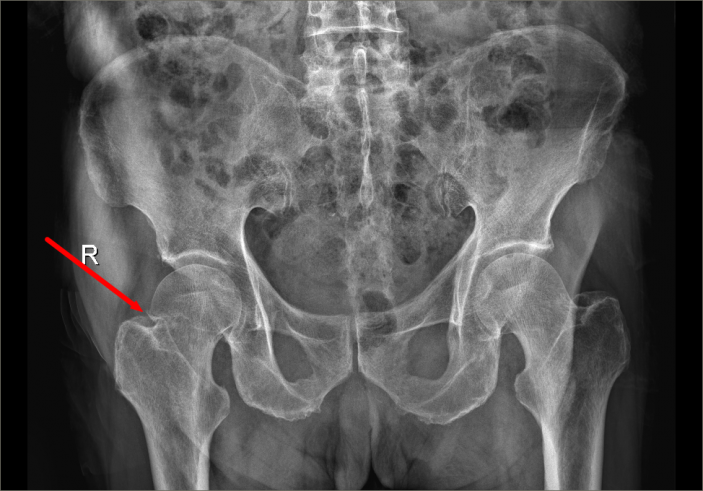

近日,骨科又收治了一位98歲高齡來自占隴鎮的股骨頸骨折患者,該名患者合并有高血壓、糖尿病、肺部感染、泌尿系感染、心律失常、後循環缺血等基礎疾病和并發症,手術治療非常棘手。

爲了手術能順利開展,骨科主任吳志斌一面邀請我院内科專家會診,對内科疾病進行積極治療,爲手術開展創造有利條件,一面召開術前讨論,精心拟定“右側人工股骨頭置換術”的手術方案,并對術中、術後可能出現的情況制定相應對策。